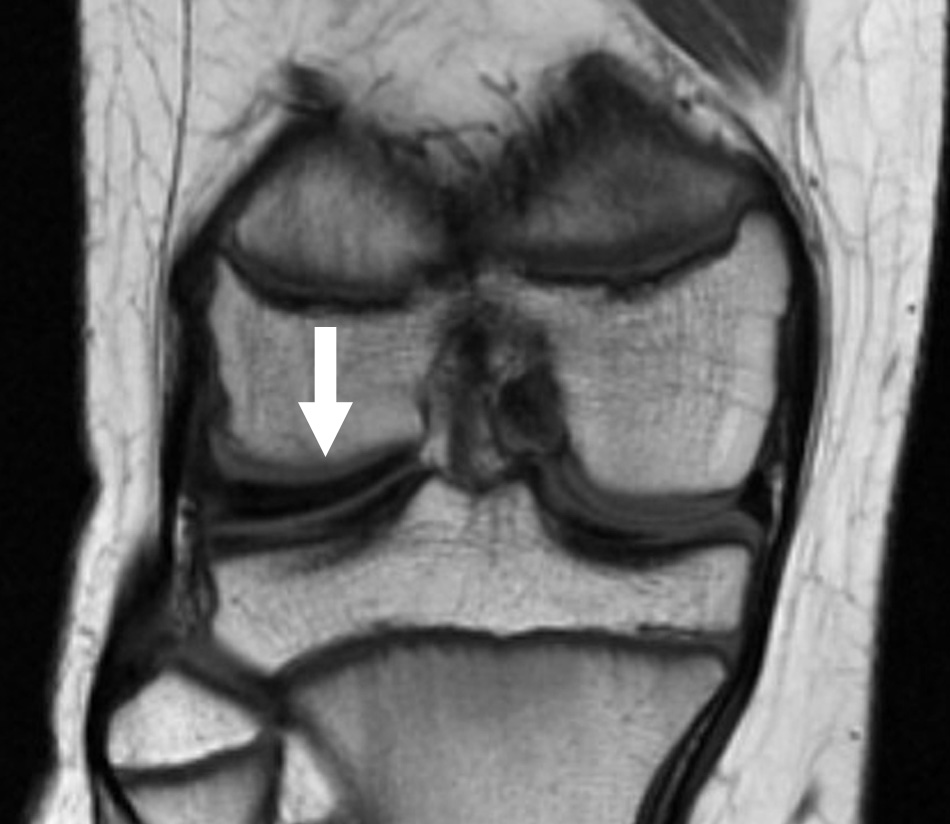

MRI of discoid meniscus

This MRI scan shows a discoid lateral meniscus (arrow). Note how much thicker the affected meniscus is when compared with the meniscus on the inside of the knee.

Reproduced from Johnson TR, Steinbach LS (eds.): Essentials of Musculoskeletal Imaging. Rosemont, IL. American Academy of Orthopaedic Surgeons, 2005, p. 554.